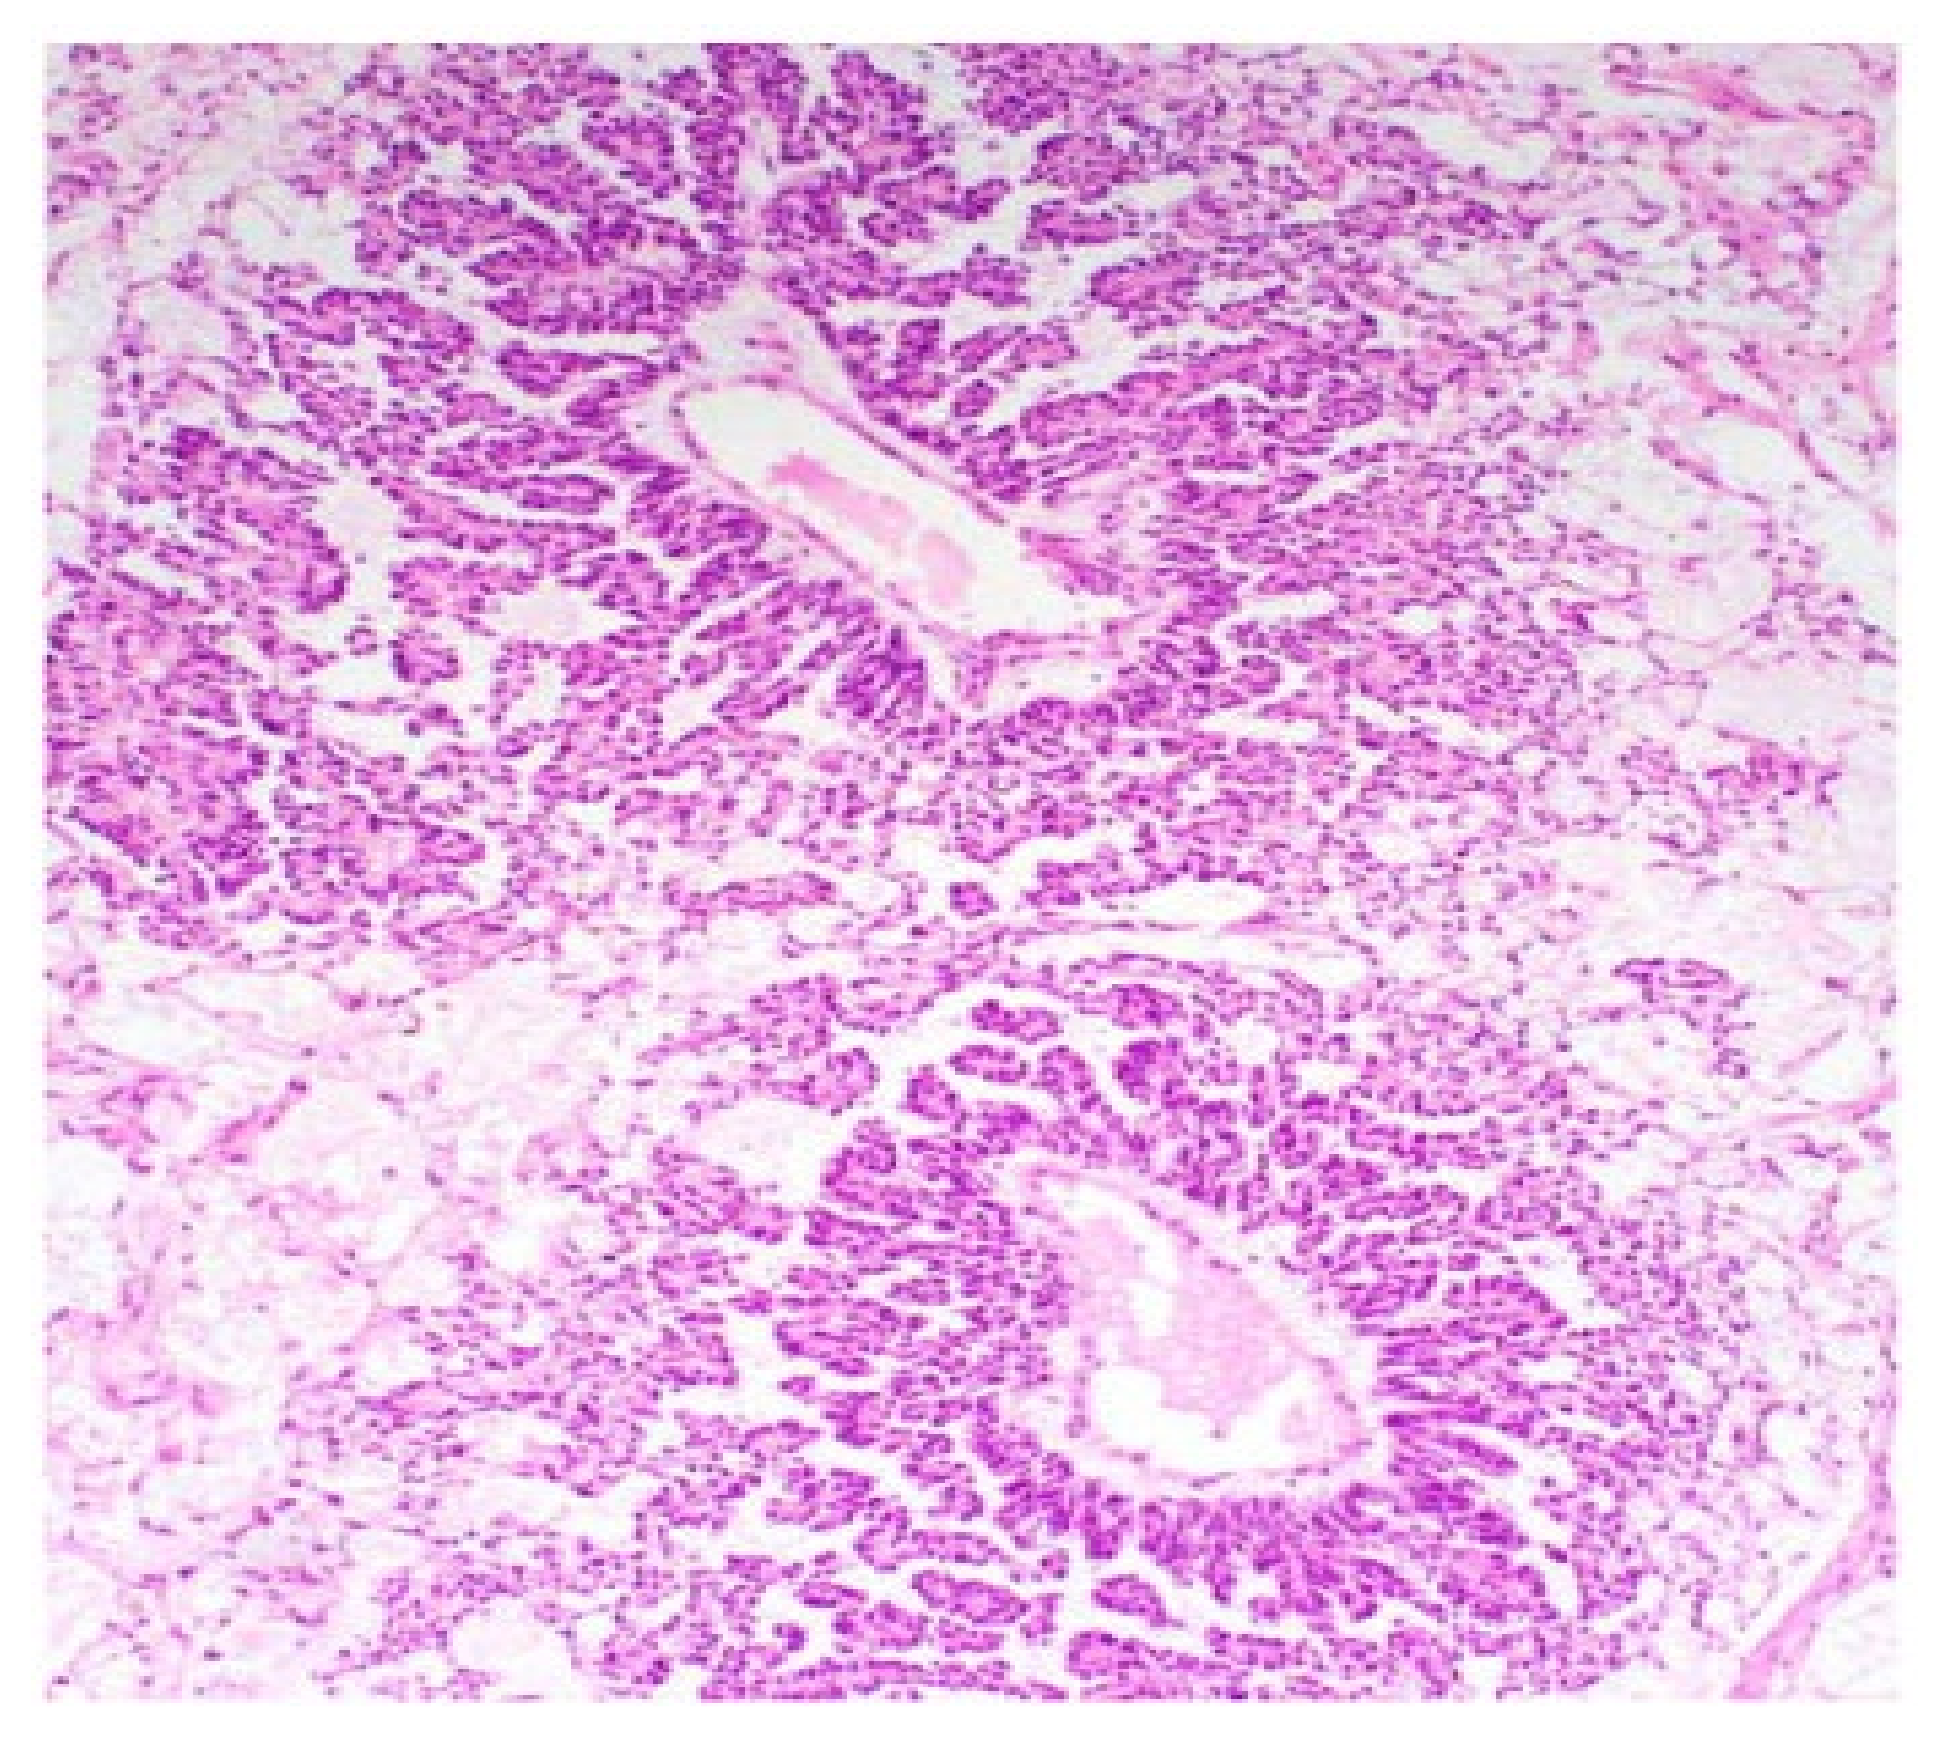

2.2. Yolk Sac Tumours

3.1. Ovarian GrCT